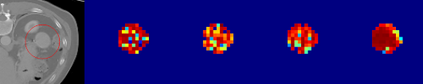

Evaluating lesion progression and treatment response via longitudinal lesion tracking plays a critical role in clinical practice. Automated approaches for this task are motivated by prohibitive labor costs and time consumption when lesion matching is done manually. Previous methods typically lack the integration of local and global information. In this work, we propose a transformer-based approach, termed Transformer Lesion Tracker (TLT). Specifically, we design a Cross Attention-based Transformer (CAT) to capture and combine both global and local information to enhance feature extraction. We also develop a Registration-based Anatomical Attention Module (RAAM) to introduce anatomical information to CAT so that it can focus on useful feature knowledge. A Sparse Selection Strategy (SSS) is presented for selecting features and reducing memory footprint in Transformer training. In addition, we use a global regression to further improve model performance. We conduct experiments on a public dataset to show the superiority of our method and find that our model performance has improved the average Euclidean center error by at least 14.3% (6mm vs. 7mm) compared with the state-of-the-art (SOTA). Code is available at https://github.com/TangWen920812/TLT.